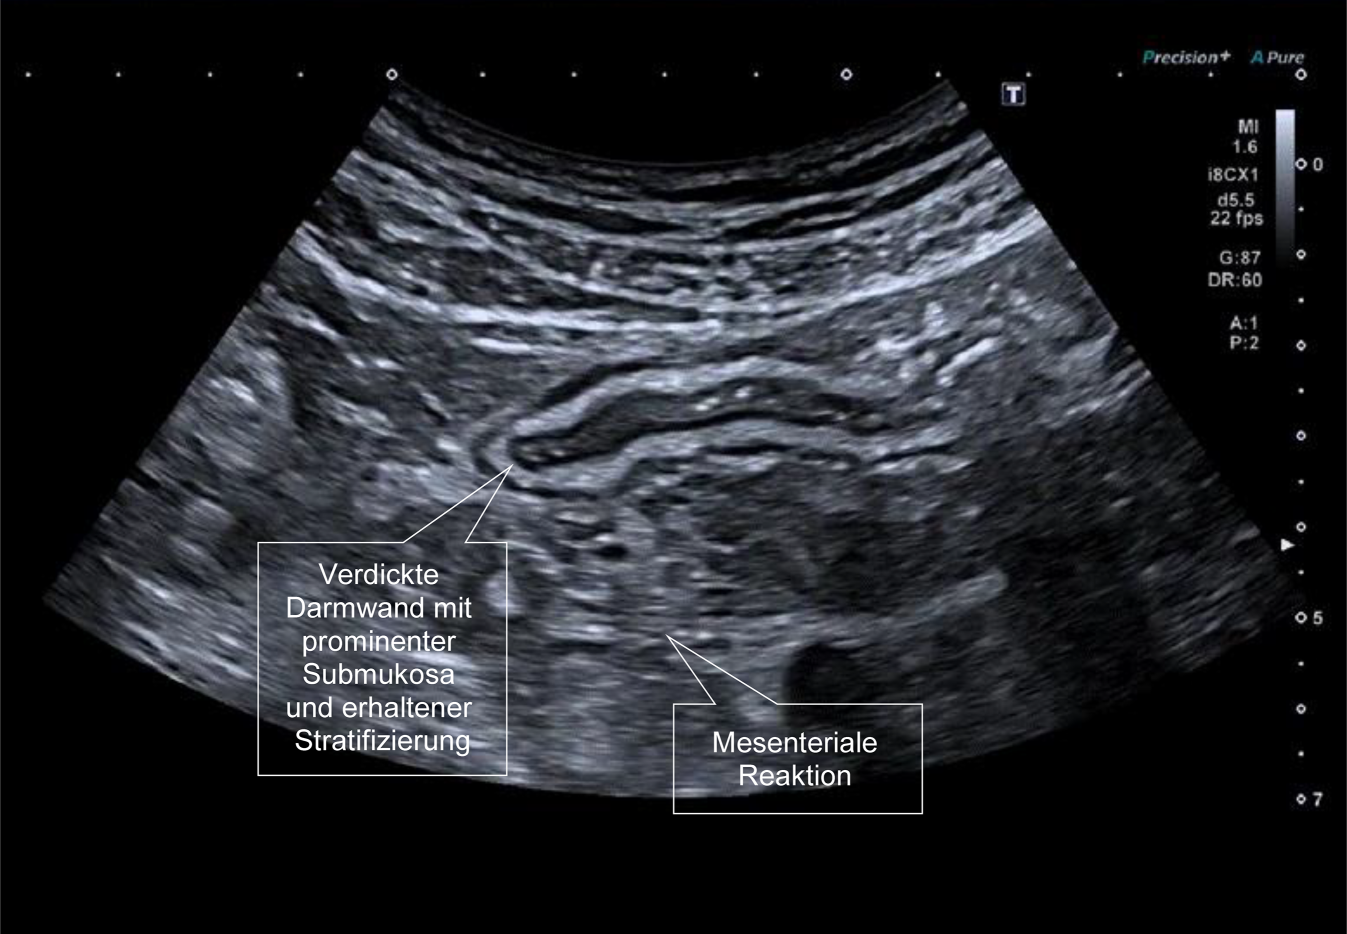

Im akuten Schub der Colitis ulcerosa oder bei chronischer Aktivität zeigt sich ebenfalls eine deutliche Verdickung der Darmwand. Die bei Colitis ulcerosa im Ultraschall sichtbaren Veränderungen sind jedoch keineswegs auf die Mukosa beschränkt. Sehr prominent zeigt sich im Ultraschall des Darms insbesondere eine Verbreiterung der Submukosa. Hier findet sich auch eine verstärkte Vaskularisierung und sicherlich ein Ödem. Ein kontinuierliches, breites Submukosa-Band ist im Darmultraschall typisch für eine aktive Colitis ulcerosa. Bei Morbus Crohn ist im Gegensatz hierzu die Submukosa zwar ebenfalls häufig verbreitert, dies jedoch unregelmässig mit zum Teil echoarmen Arealen, die vermutlich einem Entzündungszellinfiltrat in die Submukosa entsprechen (Abb. 7).

Abb. 7

58-jähriger Patient mit seit 18 Jahren bekannter Colitis ulcerosa. Nach 5 Jahren in Remission unter Vedolizumab neu aufgetretene blutige, schleimige Durchfälle nach COVID-19-Infektion. Das Sigma deutlich wandverdickt mit prominenter Submukosa bei erhaltener Stratifikation. Mesenteriale Mitreaktion als Zeichen einer deutlich aktiven linksseitigen Colitis ulcerosa. Die typische Gasfüllung im Sigma fehlt fast vollständig

Bild vergrößern